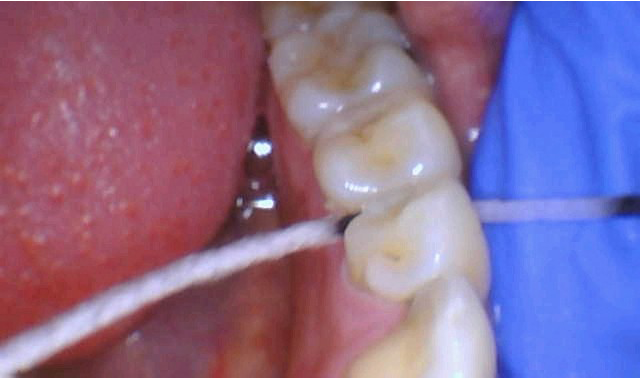

4) Or, my favorite, is apply to a marked segment of Superfloss and draw it through the contact area.

Figure 2

Figure 1

Figures 1 and 2 show his technique that he describes as the most effective method to getting the SDF directly on the interproximal surface.

Dr. Parrett and his patients like the results this treatment has provided. Additionally, he has not had any complaints of gum irritations when using this technique